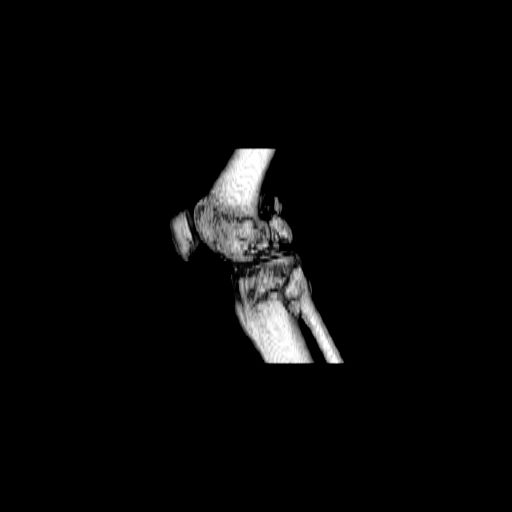

При внутрисуcтавных переломах трехмерные (3D) изображения, кроме красивого снимка, не дают полную информацию о состоянии отломков, самыми информативными являются корональные срезы на КТ и обычная длинная ренгенограмма конечности для сравнения оси конечности.

Фронтальные внутрисуставные переломы мыщельков бедра, так называемые Hoffa fracture, не частые, но встречающиеся переломы, в основном они связаны с травмой высокой энергией.